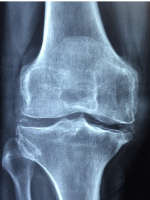

무릎 관절염 관리

무릎 관절염의 예방과 조기 발견을 위해 다음과 같은 방법을 권장합니다.

- 체중 조절: 과체중은 무릎 관절에 부담을 주고 연골의 마모를 가속화합니다. 건강한 체중을 유지하기 위해 규칙적인 식사와 운동을 해야 합니다.

- 적당한 운동: 과도한 운동은 무릎 관절에 손상을 줄 수 있으므로 적당한 강도와 시간의 운동을 해야 합니다. 특히 스트레칭이나 유산소 운동은 관절의 유연성과 혈액 순환을 도와줍니다.

- 올바른 자세: 잘못된 자세는 무릎 관절에 불균형한 힘을 가하고 연골의 손상을 촉진합니다. 앉거나 서거나 걸을 때 무릎을 과도하게 구부리거나 비틀지 않도록 주의해야 합니다.

- 정기적인 검진: 무릎 관절염은 초기에는 증상이 뚜렷하지 않을 수 있습니다. 따라서 정기적으로 무릎 관절의 상태를 검사하고 이상이 있으면 즉시 치료를 받아야 합니다.